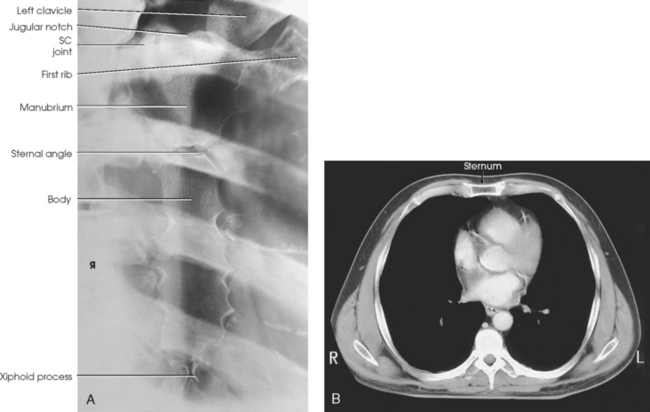

The sternum, or breastbone, is directed anteriorly and inferiorly and is centered over the midline of the anterior thorax (Figs. 9-1 to 9-3). A narrow, flat bone about 6 inches (15 cm) in length, the sternum consists of three parts: manubrium, body, and xiphoid process. The sternum supports the clavicles at the superior manubrial angles and provides attachment to the costal cartilages of the first seven pairs of ribs at the lateral borders.

The manubrium, the superior portion of the sternum, is quadrilateral in shape and is the widest portion of the sternum. At its center, the superior border of the manubrium has an easily palpable concavity termed the jugular notch. In the upright position, the jugular notch of the average person lies anterior to the interspace between the second and third thoracic vertebrae. The manubrium slants laterally and posteriorly on each side of the jugular notch, and an oval articular facet called the clavicular notch articulates with the sternal extremity of the clavicle. On the lateral borders of the manubrium, immediately below the articular notches for the clavicles, are shallow depressions for the attachment of the cartilages of the first pair of ribs.

The body is the longest part of the sternum (4 inches [10.2 cm]) and is joined to the manubrium at the sternal angle, an obtuse angle that lies at the level of the junction of the second costal cartilage. The manubrium and the body contribute to the attachment of the second costal cartilage. The succeeding five pairs of costal cartilages are attached to the lateral borders of the body. The sternal angle is palpable; in the normally formed thorax, it lies anterior to the interspace between the fourth and fifth thoracic vertebrae when the body is upright.

The xiphoid process, the distal and smallest part of the sternum, is cartilaginous in early life and partially or completely ossifies, particularly the superior portion, in later life. The xiphoid process is variable in shape and often deviates from the midline of the body. In the normal thorax, the xiphoid process lies over the 10th thoracic vertebra and serves as a useful bony landmark for locating the superior portion of the liver and the inferior border of the heart.

The sternoclavicular joints are the only points of articulation between the upper limbs and the trunk (see Fig. 9-3). Formed by the articulation between the sternal extremity of the clavicles and the clavicular notches of the manubrium, these synovial gliding joints permit free movement (the gliding of one surface on the other). A circular disk of fibrocartilage is interposed between the articular ends of the bones in each joint, and the joints are enclosed in articular capsules.

The manubriosternal joint is a cartilaginous symphysis joint, and the xiphisternal joints are cartilaginous synchondrosis joints that allow little or no movement (see Figs. 9-3, B, and 9-7, B and C).